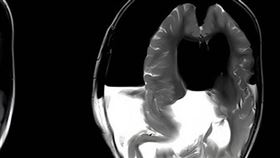

外籍男意識不清躁動 竟是「寄生蟲鑽腦」

一名外籍男子日前被送至衛福部桃園醫院急診,除了噁心嘔...

女嬰行動遲緩!檢查見「大腦寄生胎中胎」

中國發生一對「雙胞胎」其中一位竟長在姐姐頭骨內!原來...